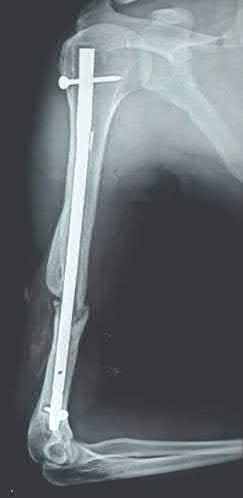

Question 9:

A 30-year-old male sustains a severe midfoot sprain. Radiographs reveal widening between the bases of the first and second metatarsals. The primary ligamentous stabilizer disrupted in this classic Lisfranc injury connects which two osseous structures?

Correct Answer: Medial cuneiform to 2nd metatarsal base

Explanation:

The Lisfranc ligament is the strongest ligament in the tarsometatarsal joint complex. It courses obliquely from the lateral aspect of the medial cuneiform to the medial base of the second metatarsal. It acts as the primary stabilizer of the second metatarsal base. Disruption results in the classic widening between the first and second rays, often with an avulsion fragment ('fleck sign').